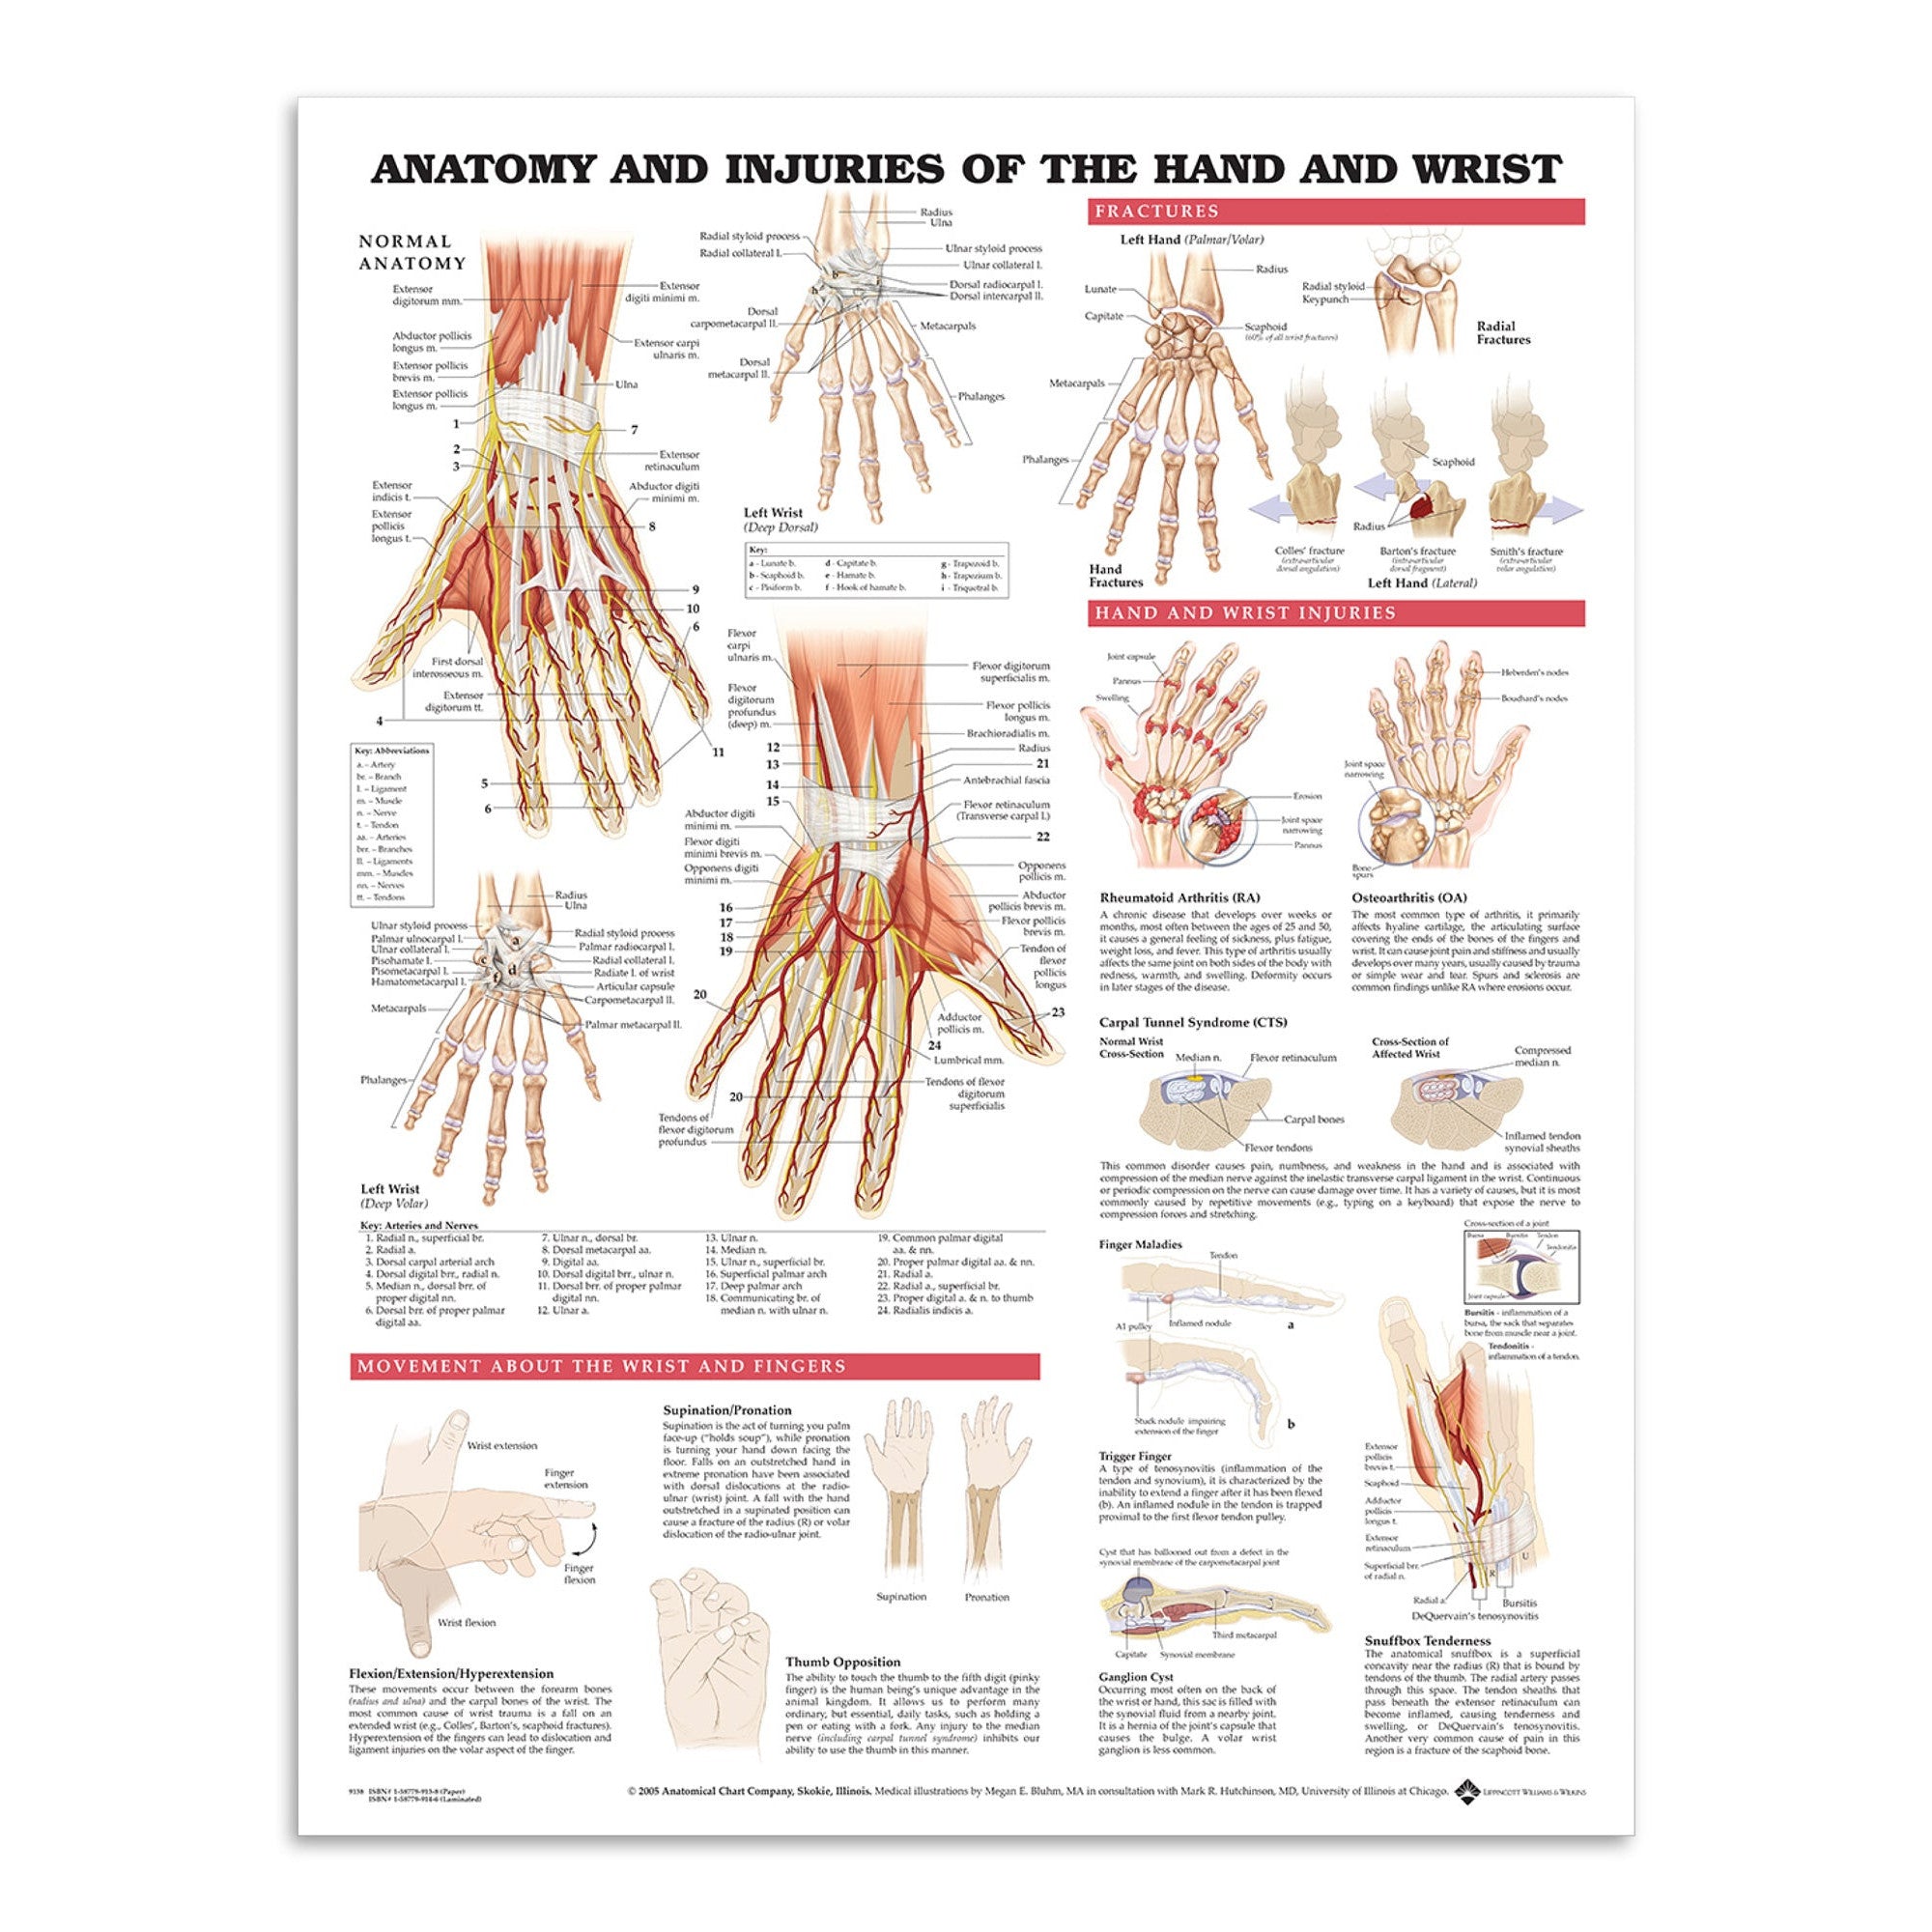

Muscle posters

Muscles provide movement to the musculoskeletal system, and their origins, insertions and lodges are clinically important for every healthcare professional. That is why we at eAnatomi have both developed and designed our own anatomy posters, which provide the ultimate overview of all the muscles of the body. On this page you can find both our own posters and posters from other manufacturers. We offer posters in several different languages such as pure Latin, Danish, English and Swedish, etc.